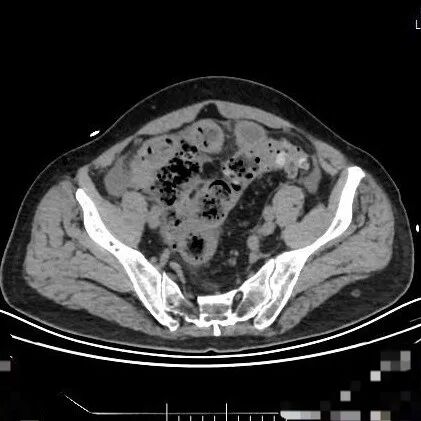

70岁的赵大叔长期便秘,但总觉得“上了年纪都这样”从未进行系统检查。直到在家中排便困难,出现腹痛并加剧才来到青岛西海岸新区中医医院肛肠科就医。 检查结果令人震惊: CT显示腹腔有游离气体,高度怀疑肠穿孔。

急诊手术中,医生发现他的结肠部位已发生恶性肿瘤并导致了穿孔。经过紧急肿瘤切除和肠道造口手术,在重症监护室恢复近一周时间才逐渐病情稳定。但后续仍需进行化疗。